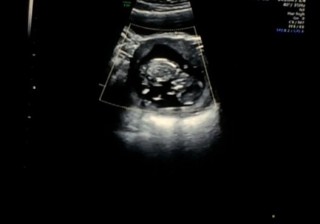

始めての腹部エコー( ´ ▽ ` ) 始めて心臓の音も聞こえて感動しました♪ 指をしゃぶったり かわいい(。-_-。) 元気に育ってね。

これは9週の時のエコーなんですが、手足をパタパタさせて元気に動いていました(-_^)☆まだ旦那さんは一緒に見れない内診だったので1人で感動の涙…。旦那さんにもみてほしかったなぁ…❤︎ママのお腹ですくすく大きくなっていく我が子に感謝感謝です。早く会いたいなぁ…来週、また元気な姿みせてね♪